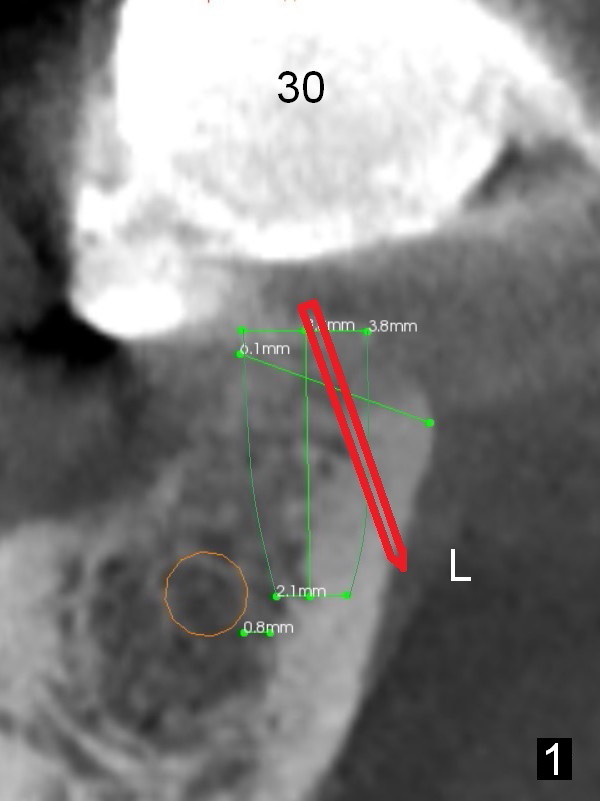

At the site of #30, the lingual plate perforates in the early stage of osteotomy (Fig.1 red arrow).  As indicated by the thick lingual plate, the osteotomy turns out to be difficult.  The trajectory is corrected immediately (Fig.2 red) and with control so that the Inferior Alveolar Canal (brown circle) will be not be violated.  The perforation is repaired with Osteogen plug (Fig.3 white) and nearby autogenous bone (red circles) before placement of a 3.8x8 mm implant (green).